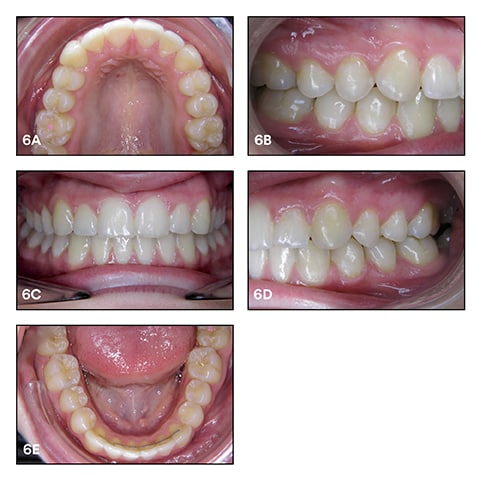

Images taken during a check-up in October 2017 revealing a successful treatment with stable outcomes. See Figure 6a-e.

By using Clarity Advanced Ceramic Brackets in combination with the selected archwires and ligatures, we were able to open the space for the upper canines and integrate them into the arch without intrusion of the other teeth. The torque with the ceramic was nicely expressed without any fracture of the ceramic bracket material. A nice Class-I relationship with good overjet and overbite was achieved. Finally, we succeeded in greatly improving the smile line of the patient.